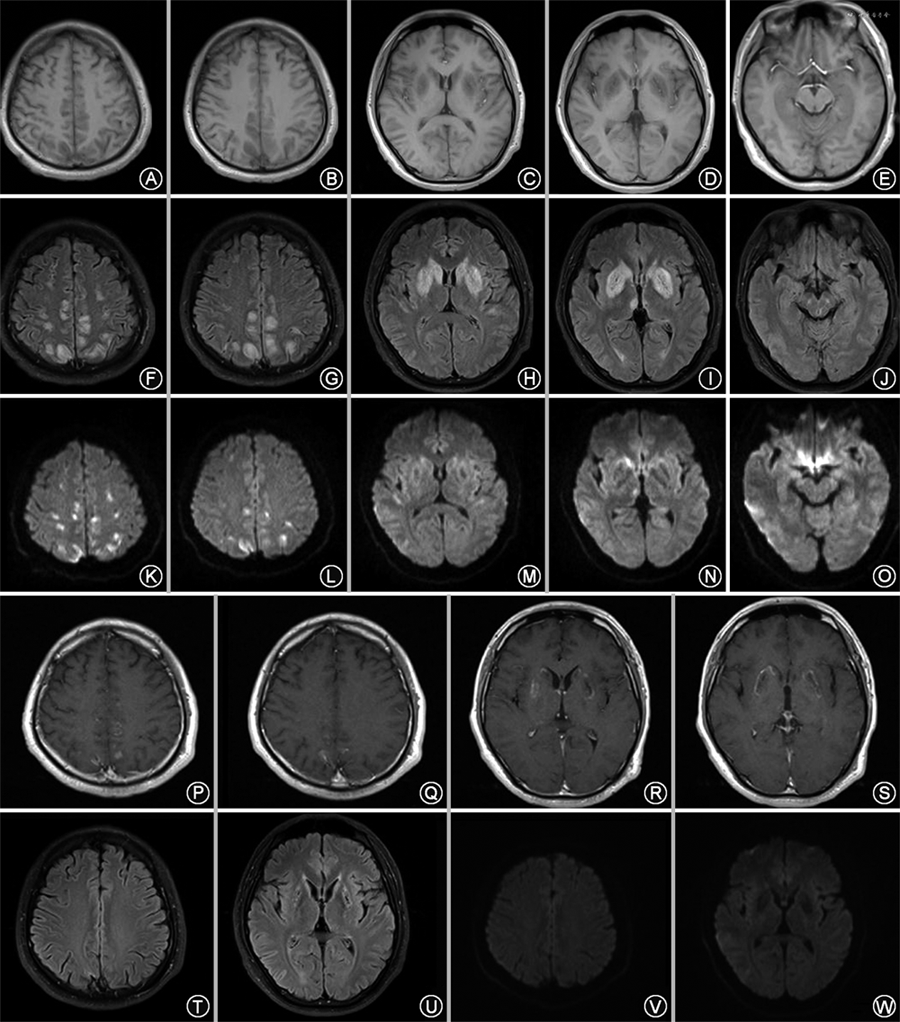

患者男性,29岁,因“发作性肢体抽搐3 d”于2019年12月13日于南京医科大学附属无锡人民医院神经内科住院。患者于3 d前出现左上肢抽搐,持续数十秒,伴左手麻木无力;2 d前出现右上肢抽搐2次,每次持续1 min左右,在当地医院就诊过程中出现发作性意识丧失,双眼向右凝视,牙关紧闭,四肢抽搐2次,每次持续1 min左右缓解。头颅CT:双侧基底节区可疑稍低密度影;头颅CTA:大血管未见明显狭窄。发病以来无感染、发热,无外伤、疫苗接种史,体重无明显下降。既往病史:7岁时有症状性癫痫、昏迷病史,当时考虑疑似脑干脑炎。父母体健,为姨兄妹近亲结婚,母亲有1次无明显原因流产史。体格检查:生命体征平稳,头发稀疏,色偏黄,其他内科体格检查未见明显异常。神经系统体格检查:意识清楚,双侧眼球向内、向上、向下活动受限,双眼水平眼震,右侧鼻唇沟浅,四肢肌力Ⅳ级,四肢肌张力、腱反射、深浅感觉正常,双侧指鼻试验不准,双侧跟膝胫试验不准,双侧病理征、脑膜刺激征阴性。辅助检查:(1)实验室检查:天冬氨酸氨基转移酶107 U/L(正常值15~40 U/L),丙氨酸氨基转移酶40 U/L(正常值9~50 U/L),乳酸脱氢酶325 U/L(正常值120~250 U/L),肌酸激酶8 498 U/L(正常值50~310 U/L),肌酸激酶-MB同工酶17.9 U/L(正常值0~12 U/L),风疹病毒抗体-IgG 15.50 IU/ml(正常值0~10 IU/ml),维生素B12 75 pmol/L(正常值133~675 pmol/L),叶酸 4.09 nmol/L(正常值7.0~45.1 nmol/L),同型半胱氨酸 33.40 μmol/L(正常值4.0~15.4 μmol/L),风湿免疫指标、肿瘤指标、甲状腺功能及相关抗体、铜蓝蛋白、血乳酸、血气分析结果均在正常范围。(2)腰椎穿刺:测压正常,脑脊液常规、生化、病原学检查、免疫球蛋白水平均在正常范围。(3)尿液有机酸分析:甲基丙二酸正常。(4)腹部超声、心脏超声、肌电图检查未见明显异常;动态脑电图:尚在正常范围内(基本节律以低幅β波为主)。(5)头颅MRI:脑干、双侧尾状核、豆状核、丘脑、额颞顶叶、右侧枕叶皮质下异常信号,呈T1低信号(图1A~E)、液体衰减反转恢复序列(FLAIR)高信号(图1F~J),部分弥散加权成像(DWI)高信号(图1K~O);增强头颅MRI:增强后双侧额顶皮质部分病灶可见斑片状强化,双侧基底节区病灶可见结节状及环状强化(图1P~S);磁共振波谱:基底节感兴趣区胆碱峰轻度升高,N-乙酰天冬氨酸峰轻度减低,未见脂质峰或乳酸峰(图2)。(6)基因检测:经知情同意后抽取患者及其父母外周静脉血3 ml,应用二代目标区域捕获测序与Sanger测序验证发现SLC19A3基因的NM_025243:C.1066A>C纯合变异(图3A),其父母该位点均为杂合变异(图3B、C),该变异发生在第4号外显子区,使得第356位的天冬酰胺变异为组氨酸。应用PolyPhen-2预测该变异,结果为致病性的,MutationTaster、SIFT、LR、RialSVM等预测该变异为良性的或可耐受的,目前未见该变异在相关文献或数据库中的报道。

患者据基因结果及临床表型确诊为BTBGD,予口服丙戊酸钠缓释片、生物素、维生素B1、甲钴胺、叶酸治疗,患者无肢体抽搐发作,四肢肌力明显改善。出院后继续口服上述药物治疗。随访:3个月后复查维生素B12 730 pmol/L,叶酸 41.50 nmol/L,同型半胱氨酸、肌酶谱在正常范围。复查头颅MRI:脑干、双侧尾状核、豆状核、丘脑、额颞顶叶、右侧枕叶皮质下异常信号消退(图1T~W)。5个月后患者出现右脚趾不自主跖曲,不能奔跑,复查头颅MRI结果与3个月时无明显变化,脑电图在正常范围,考虑存在肌张力障碍症状,加用多巴丝肼片+普拉克索+巴氯芬口服后,症状缓解。

在我们的病例中,患者第一次头颅MRI显示病变范围累及脑干、双侧尾状核、豆状核、丘脑、额颞顶叶和右侧枕叶皮质下,癫痫发作考虑与额颞顶叶皮质神经元病变有关;四肢肌力下降考虑与双侧尾状核、豆状核病变引起双侧内囊部分性损害累及了双侧皮质脊髓束有关;眼球运动障碍考虑为中脑病变导致的核性眼肌麻痹(图1J),但患者双侧的丘脑中脑结合处(右侧严重)也存在病变。已有文献报道,单侧丘脑中脑结合处病变可导致多种眼位异常和眼球活动障碍[7],但其具体的神经解剖学机制目前仍然未被完全阐明,本例患者的眼球运动障碍考虑与此病变也有关联。本例患者叶酸水平较低,已有研究结果表明:叶酸转运体(SLC19A1基因编码)与运输硫胺素的THTR1、THTR2为同一溶质载体家族,该家族成员介导的底物运输由跨细胞H+/OH-梯度激发,在生理pH值下可还原叶酸为阴离子,硫胺素是阳离子[8]。虽然THTR2并不直接转运叶酸,但我们分析SLC19A3基因突变导致硫胺素转运障碍影响跨细胞H+/OH-梯度,进而影响了叶酸的转运。